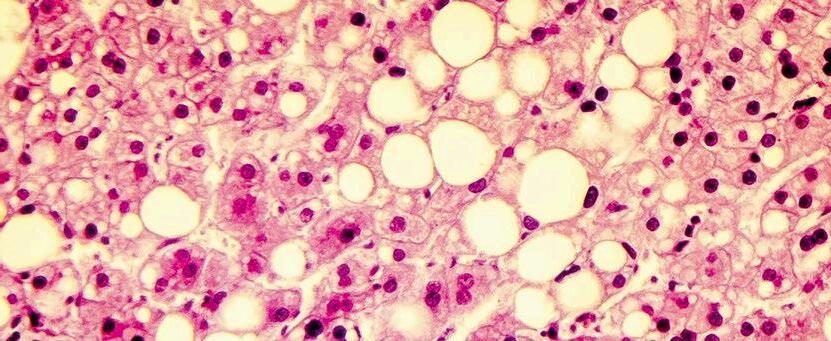

Two neoplastic viral diseases, Marek's disease and Lymphoid Leukosis, represent major threats.

Marek's disease causes tumor infiltrations in various organs and presents variable nervous symptoms, while lymphoid leukosis mainly affects the bursa of Fabricius, liver, spleen, kidney, and ovary, but does not infiltrate the peripheral nerves. It is essential to train rural veterinarians to protect non-technified poultry farming.

The lesions of Marek's disease consist of five types of tumor cell infiltrations, which are:

Visceral: Ivory-white or grayish nodules in organs such as the liver, kidney, spleen, heart, ovary, proventriculus, and lungs. They can be observed from the fourth week of age in acute cases, without involving the spinal cord or peripheral nerves

Cutaneous: Protruding masses in the feather follicles .

Muscular: White nodular masses in the pectoral muscles, although these are rare.

Neural: Affects between 20-40% of birds and is the most common form. The lesions are unilateral and are found in nerve plexuses ( brachial, lumbosacral, sciatic). The affected nerves thicken, turning yellow or pearly gray and losing their striations. The mesenteric and cranial nerves may also be affected.

Ocular: These are not described in detail, but usually include changes in the iris and other eye tissues, which are typical of the disease.

The characteristic lesions of lymphoid leukosis are mainly tumors that occur in various viscera. The most important points are:

Characteristics of tumors:

They are nodular in shape and are white, yellow, or gray.

Location of tumors:

The tumors occur most frequently in the following organs:

Liver

Spleen

Heart

Kidneys

Lungs

Ovary

Fabricius sac (almost always affected).

Tumors in the Fabricius sac:

The early tumors can be detected from 10 weeks of age.

They are characterized by a marked thickening of one or more folds of the inner wall of the sac.

Liver lesions:

In the liver, tumor lesions may be infiltrative rather than nodular.

They manifest as marked hepatomegaly (enlargement of the liver). (Figures 4 and 5)

5. Creole hen affected by lymphoid leukosis presenting diffuse nodular neoplastic infiltration of the apical lobe of the right kidney. Note that the nerve plexuses are normal.

4. Creole hen affected by lymphoid leukosis presenting severe hepatomegaly and small whitish nodules distributed multifocally.